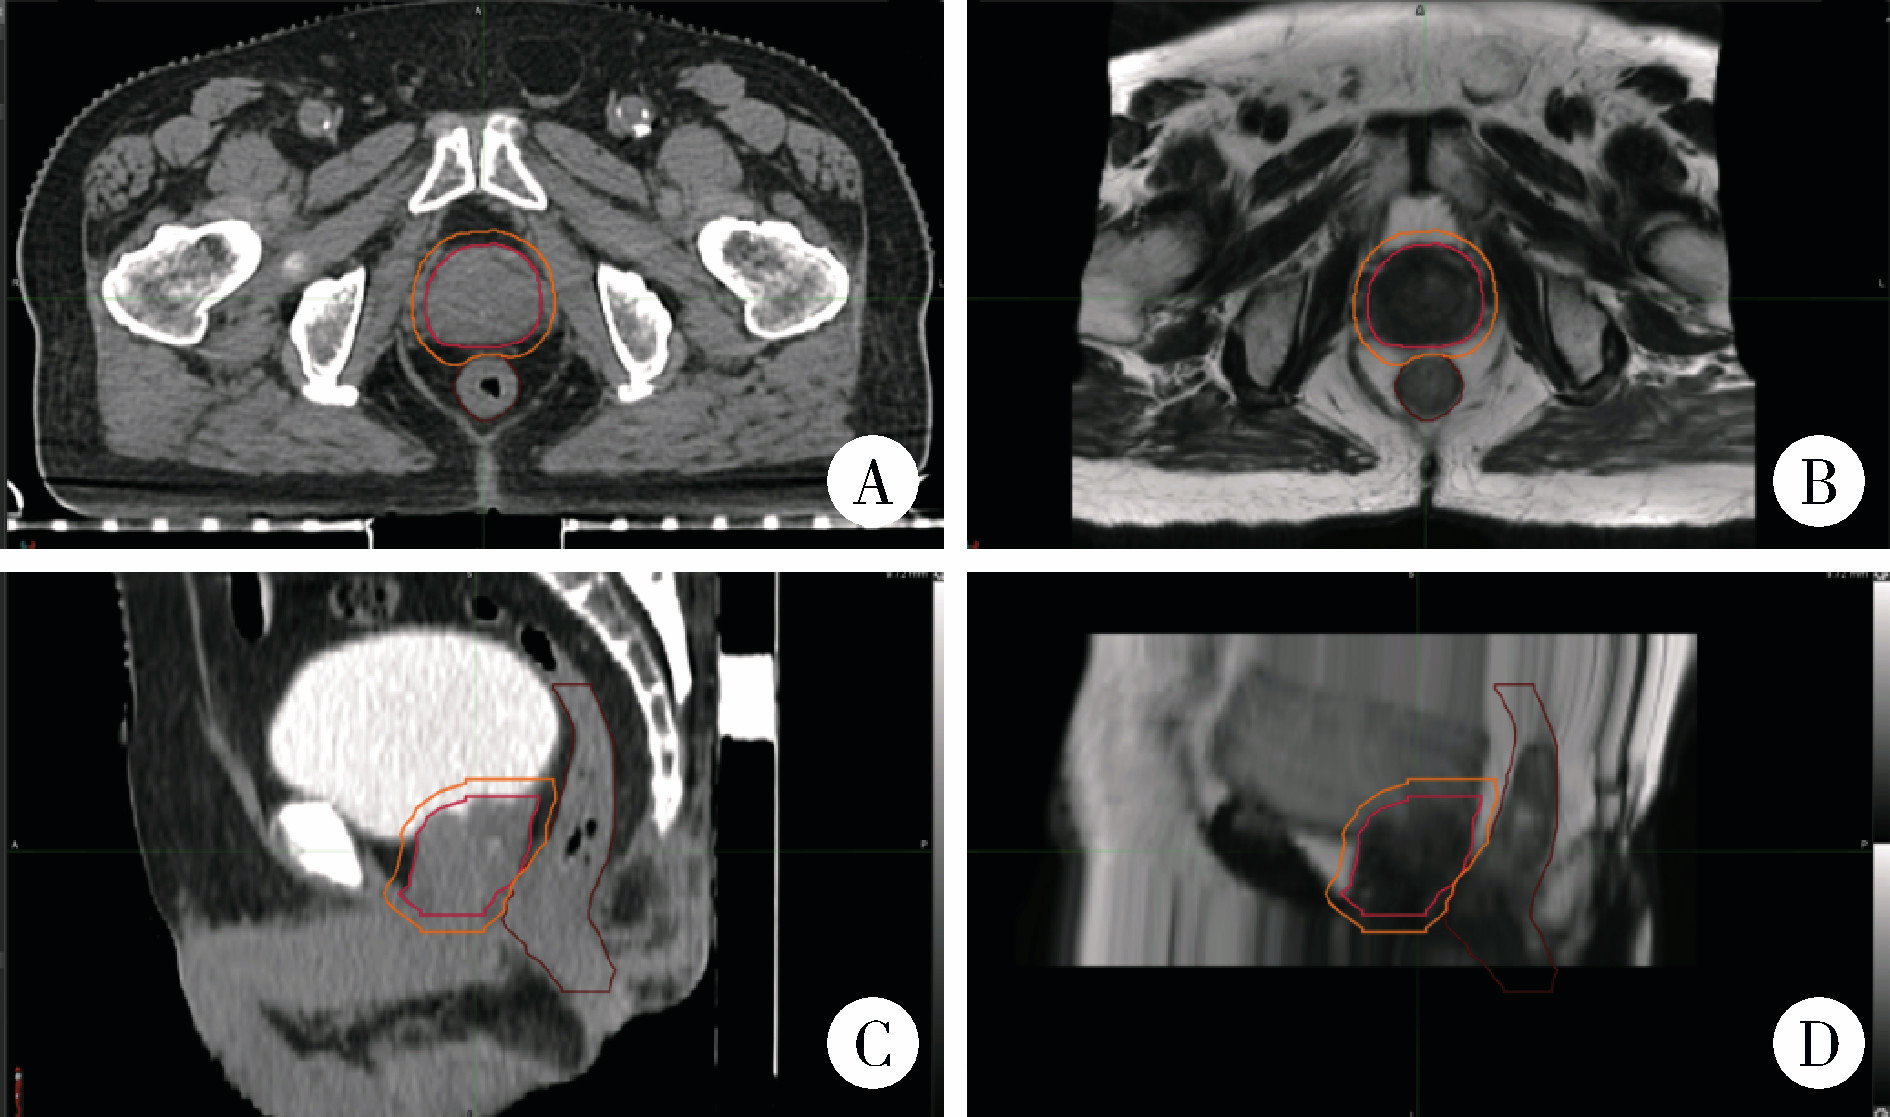

2.3 位移误差累积分布

X轴和Z轴方向上,B组位移误差在0.5 cm内的累积分布比例显著高于A组(P < 0.01)。Y轴方向上,B组摆位误差位移量在0.5 cm以内的累积分布比例虽有增高趋势,但差异无统计学意义(P=0.055, 表 2)。A组与B组在三个方向上的摆位误差累积分布见图 4, 可见B组在三个方向上的累积分布曲线均比A组更陡峭,即B组摆位误差数据更加集中于较小的范围,误差分布更稳定、集中。

图4 A、B组摆位误差的累积分布

Figure 4 Cumulative distribution of setup errors in groups A and B

A, cumulative distribution probability of setup errors in the X-axis direction; B, cumulative distribution probability of setup errors in the Y-axis direction; C, cumulative distribution probability of setup errors in the Z-axis direction.